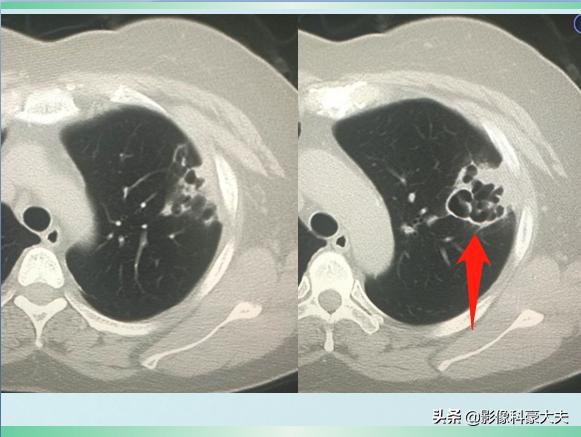

一开始,是星星点点的点片状影,很快融合成大片实变影,并发生多发小坏死,形成小脓肿。并且它的坏死组织像果冻一样很粘稠,不容易咳出来,呈很有特点的“砖红色”:

1.大多位于一侧上肺,或双下肺后基底段,如果是多发的病灶,这两个部位也是重点区域 2.根据影像特点分4型,实变病灶内无支气管通气征;实变病灶外见气管壁增厚,病变早期就可见坏死或空洞,直径不超过2cm,少量胸腔积液常见50%,脓胸不常见20%以下,无坏死的密度均匀,边界清楚,朵朵白云状,巨大病灶占据一叶,有膨胀感,钟乳石征,坏死呈蜂窝状。(来自通化市中心医院唐绍宏教授的总结)

这是一位62岁的退休教师,因为淋雨受凉后出现高热、胸痛、咳嗽症状,自服感冒药无效,在家里拖了3天才过来,已经是重症肺炎,肺组织广泛坏死了,后来没有抢救回来……